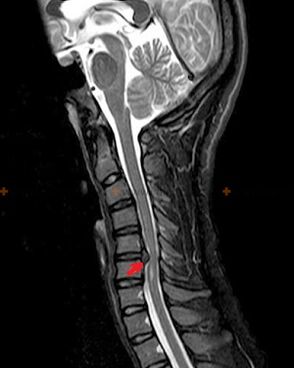

Diagnostics and X-ray signs

Osteochondrosis is an X-ray diagnosis, because a detailed clinical picture can only occur at the moment when it becomes acute, changes in the back can occur with the complete subjective well-being of a person.Without X-ray examination, we can talk about osteochondrosis only suspiciously, because similar symptoms can be caused by other diseases (myositis, spinal neoplasms, etc.).

The following research methods are used to diagnose osteochondrosis: radiography (preferably functional tests), MSCT and MRI.The last case is the most superior because it allows you to visualize the state of the intervertebral structures very clearly.

The presence of the changes described above, changes in the structure of the intervertebral disc detected by MSCT and MRI serve as reliable signs confirming the presence of osteochondrosis.